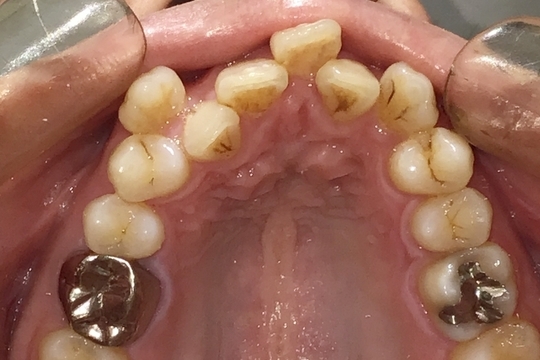

Before

浜松市中央区・自動車学校前駅のインビザラインの症例

Y.S. 30代男性

全体的にガタガタしているのが気になるという主訴だったため、上下左右第一小臼歯を抜歯し、叢生を並べました。

治療の期間:R3. 9/1〜R5. 10/31

治療の価格:88万円